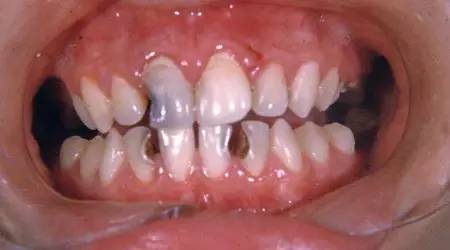

2、龋齿

据美国疾病预防和控制中心(CDC)统计,美国有1/4的成年人患有未治疗的龋齿,某些时候,几乎每一个成年人都有龋齿

下列情况下,你可能患有龋病:牙痛、食物嵌塞、舌头感觉到牙齿粗糙、吃冷或甜食时感到疼痛。

根据龋齿的严重程度,可以采用充填、冠修复或根管治疗。如果龋损太大,或有神经损伤,有可能需要拔除牙齿。

为了减少患龋的风险,应每天刷牙两次,使用牙线一次,使用含氟牙膏,远离含糖的食物和饮料,定期看口腔医生。